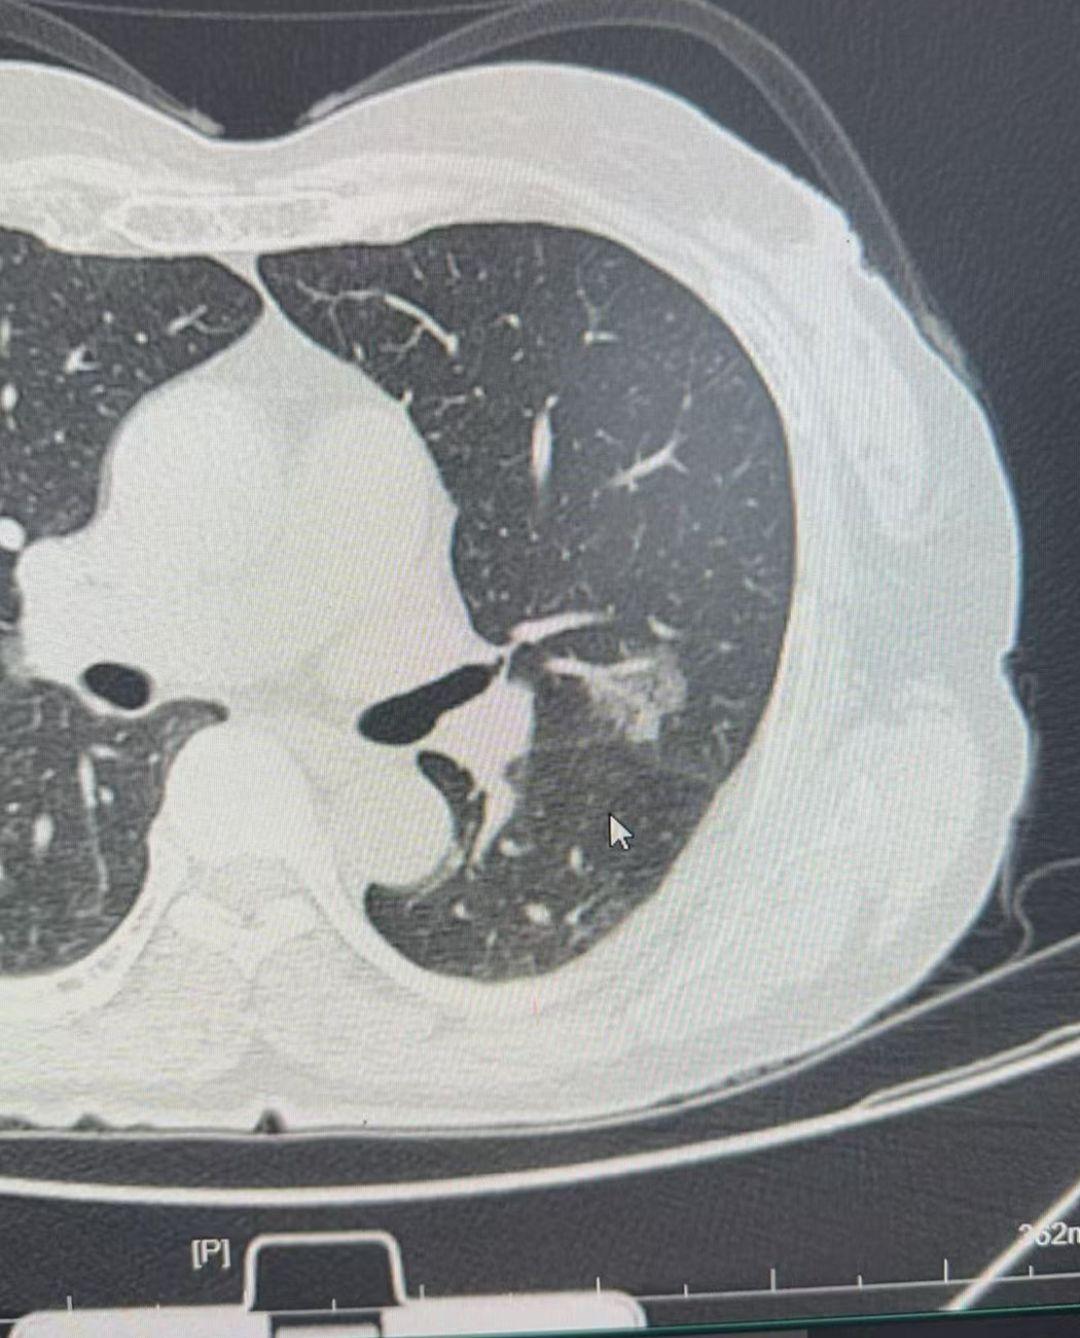

图识肺结节……图识肺结节……可以如图发在评论区,我会抽空回复……

这个8mm的微浸润腺癌,看了很多地方没看出来,我们团队没有漏掉这个恶性...

如何高效的看肺结节?来门诊找我看肺结节先弄清楚几个问题:第一,结节大小...

高龄的磨玻璃结节,随访也是一个选择……86岁高龄女性,右上肺尖段持续存...